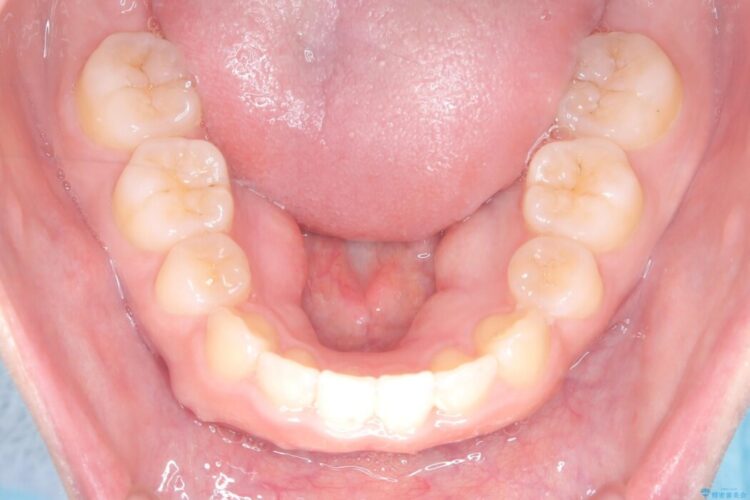

抜歯で得たスペースを活用し、大きく傾いた前歯の角度を修正しながら、ゆっくりと後方へ移動させていきました。

抜歯スペースが閉じるにつれて、唇側の圧迫感が解消され、口元のボリュームが自然に抑えられていきました。

治療後は、口元の突出感が解消され、鼻先から顎先を結ぶ「Eライン」が劇的に変化し「自信を持って笑えるようになった」と大変喜んでいただけました。